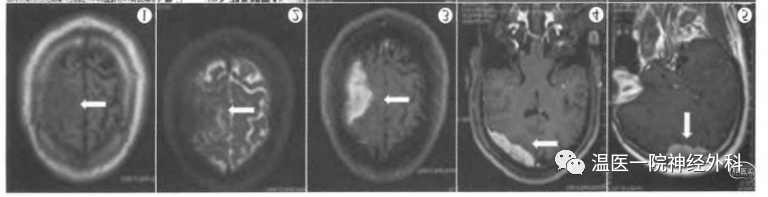

Case1[2]:T1右顶叶等信号病变,边界较清。T2右顶叶低信号病变,周围脑组织水肿。轴位增强MR病变边界清楚,明显强化,可见少许低信号区。矢状位增强可见脑膜尾征。

Case2[3]: CT均匀高密度。MR显示病变边界清晰,呈均匀强化,有脑膜尾征。